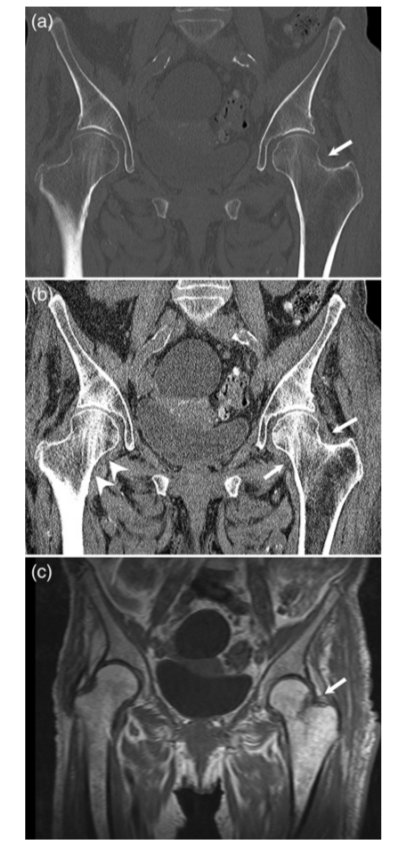

病例6 一例82岁髋部外伤患者,非移位股骨颈骨折,在CT横断面可见积脂血症,MR证实股骨颈骨折。关节积脂血症在非移位股骨颈骨折的识别中作用明显。